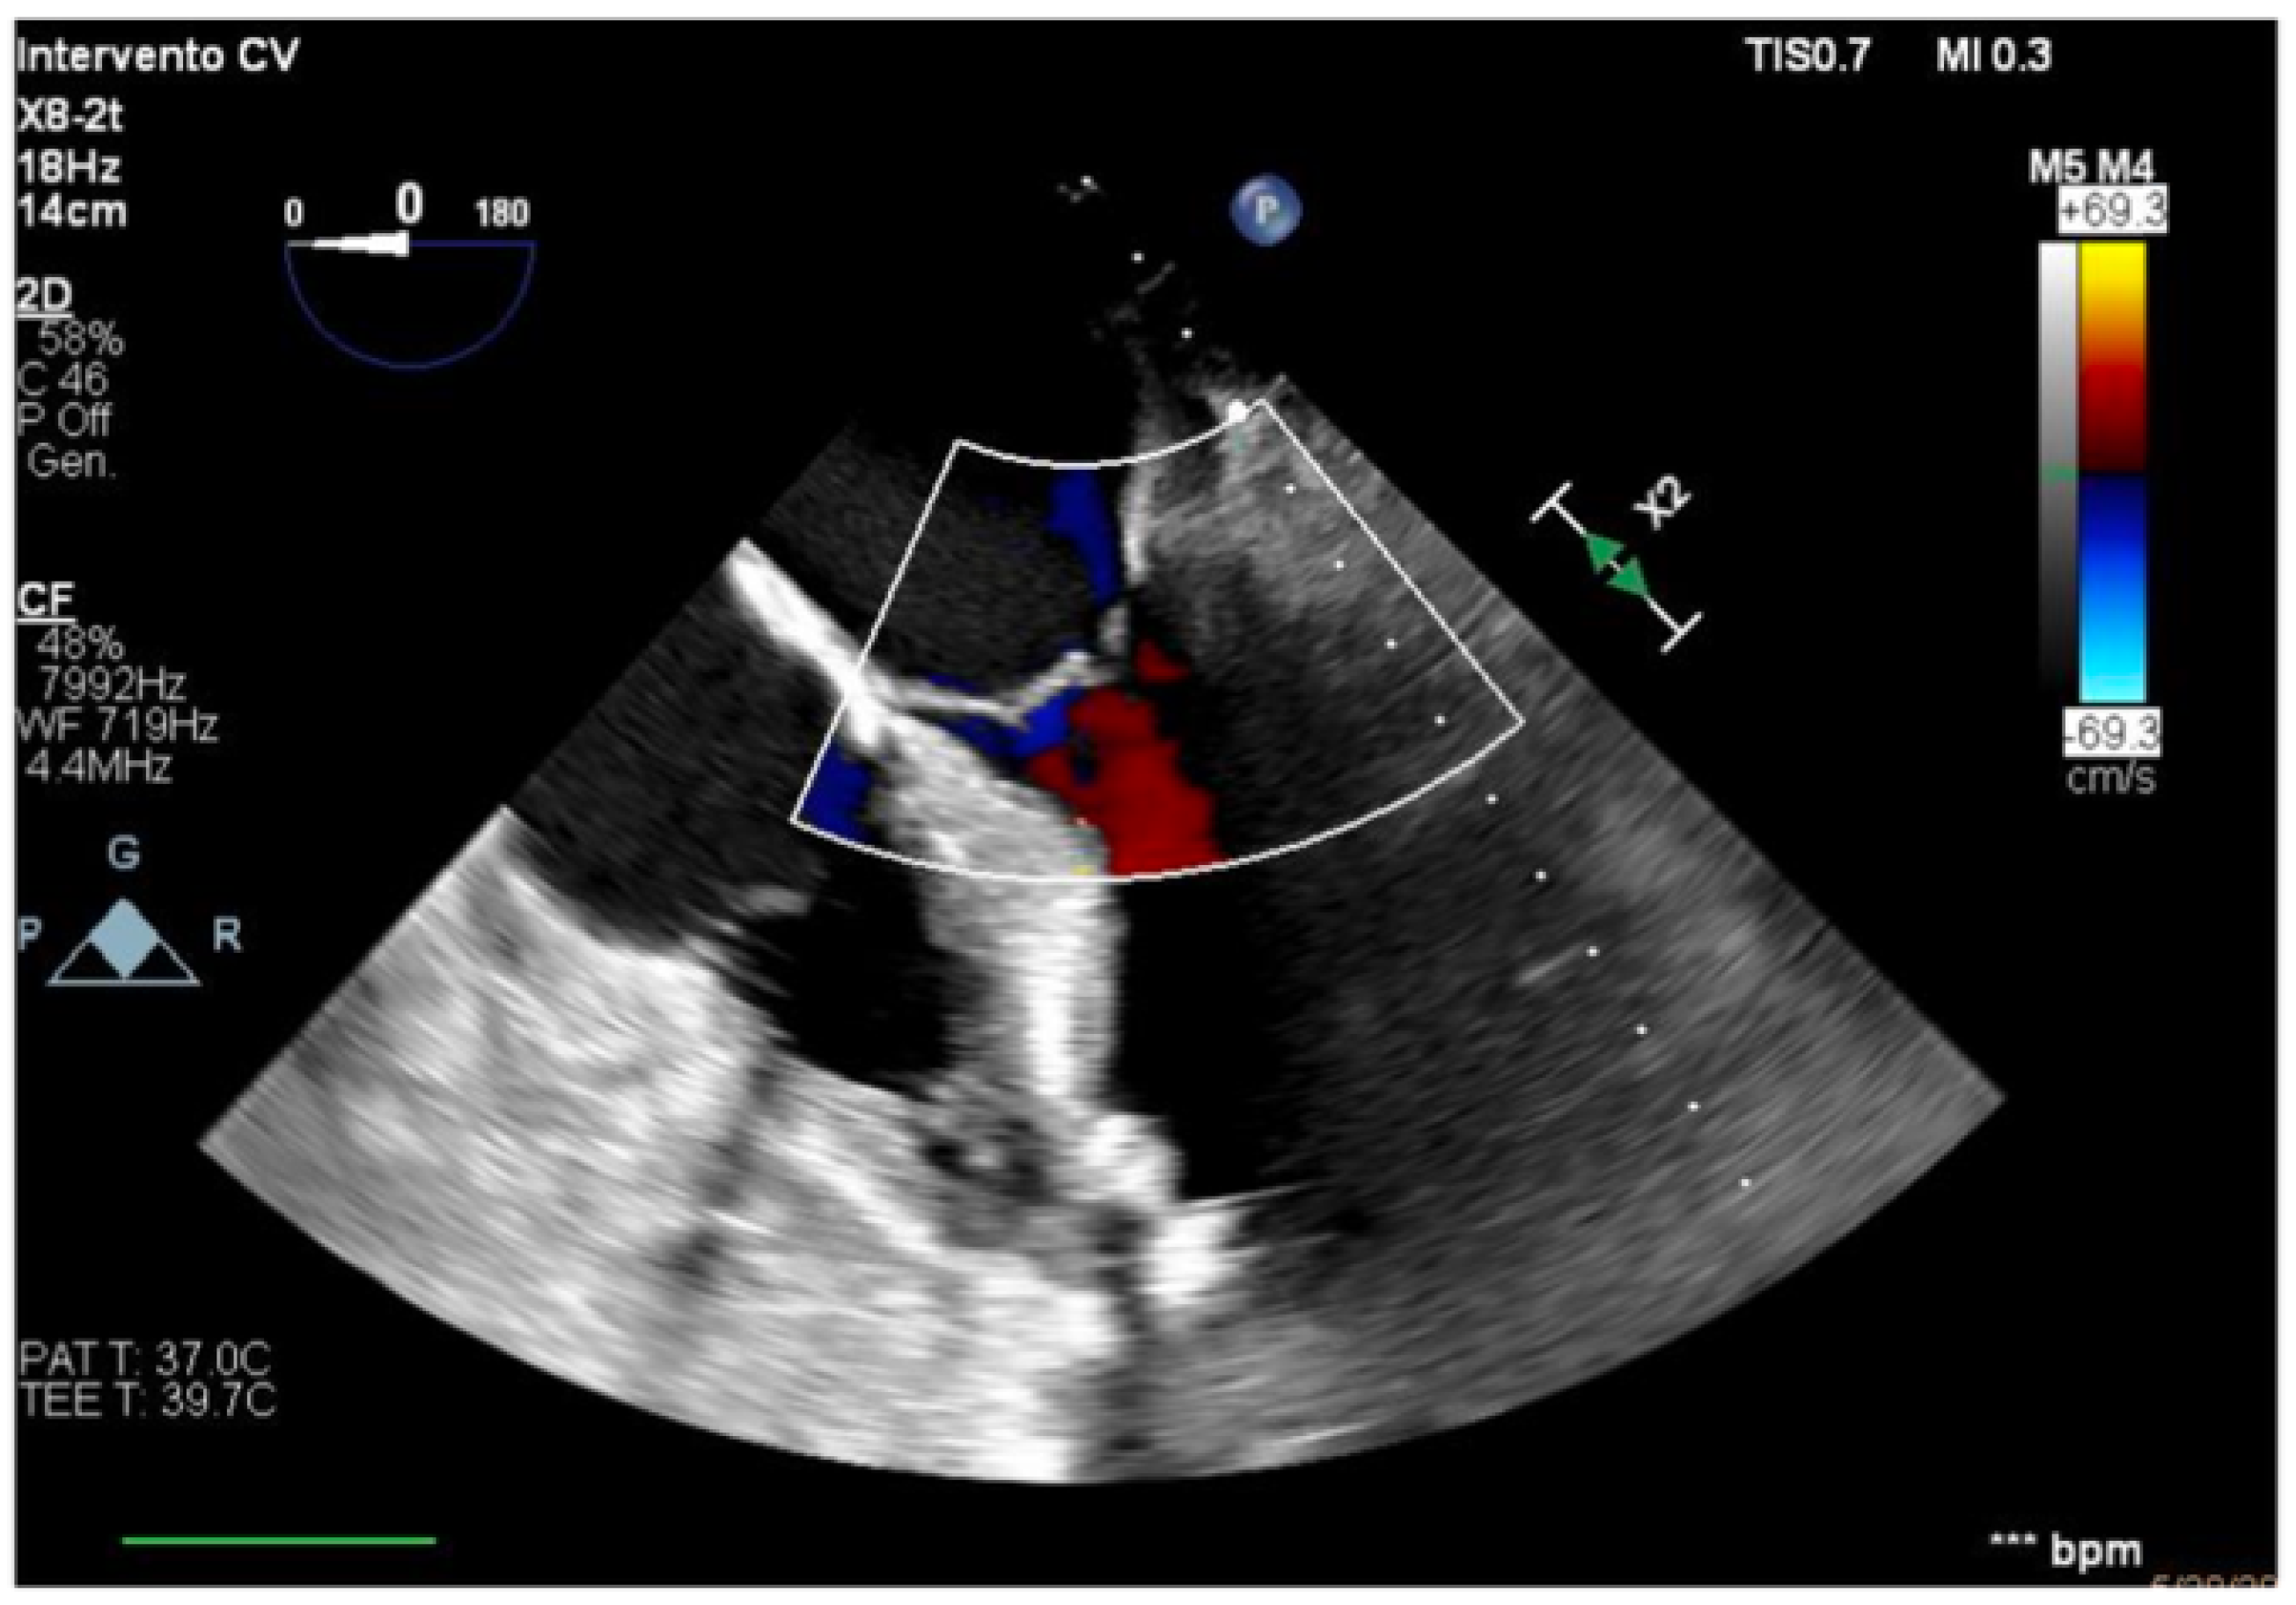

We describe a case of a 75-year-old woman affected by a post-myocardial-infarction ventricular septal defect (VSD) and a left-ventricle (LV) apical aneurysm. The patient underwent surgery for VSD closure and aneurysm exclusion. The patient had a STEMI (ST-elevation myocardial infarction), with evidence of occlusion of the anterior interventricular artery, for which thrombus aspiration and stenting of the left coronary artery and proximal anterior interventricular artery was performed. Then, she developed cardiogenic shock with pulmonary edema and thus required the support of an IABP (intra-aortic balloon pump) of C-PAP and levosimendan in continuous infusion for 24 h. Seven days after the event, a large post-infarct VSD at the apical level with a left–right shunt occurred. She was therefore transported from the spoke center to our hospital and underwent surgical treatment, namely, post-infarct VSD closure and exclusion of a left ventricular aneurysm. The intra-operative transesophageal echocardiography showed concentric LV remodeling, slight dilatation, LVEF 28% (Figure 1), and akinesia of the mid-apical segments in toto with aneurysmal evolution (Figure 2).

Figure 2. Trans-gastric view, apical level (short axis).